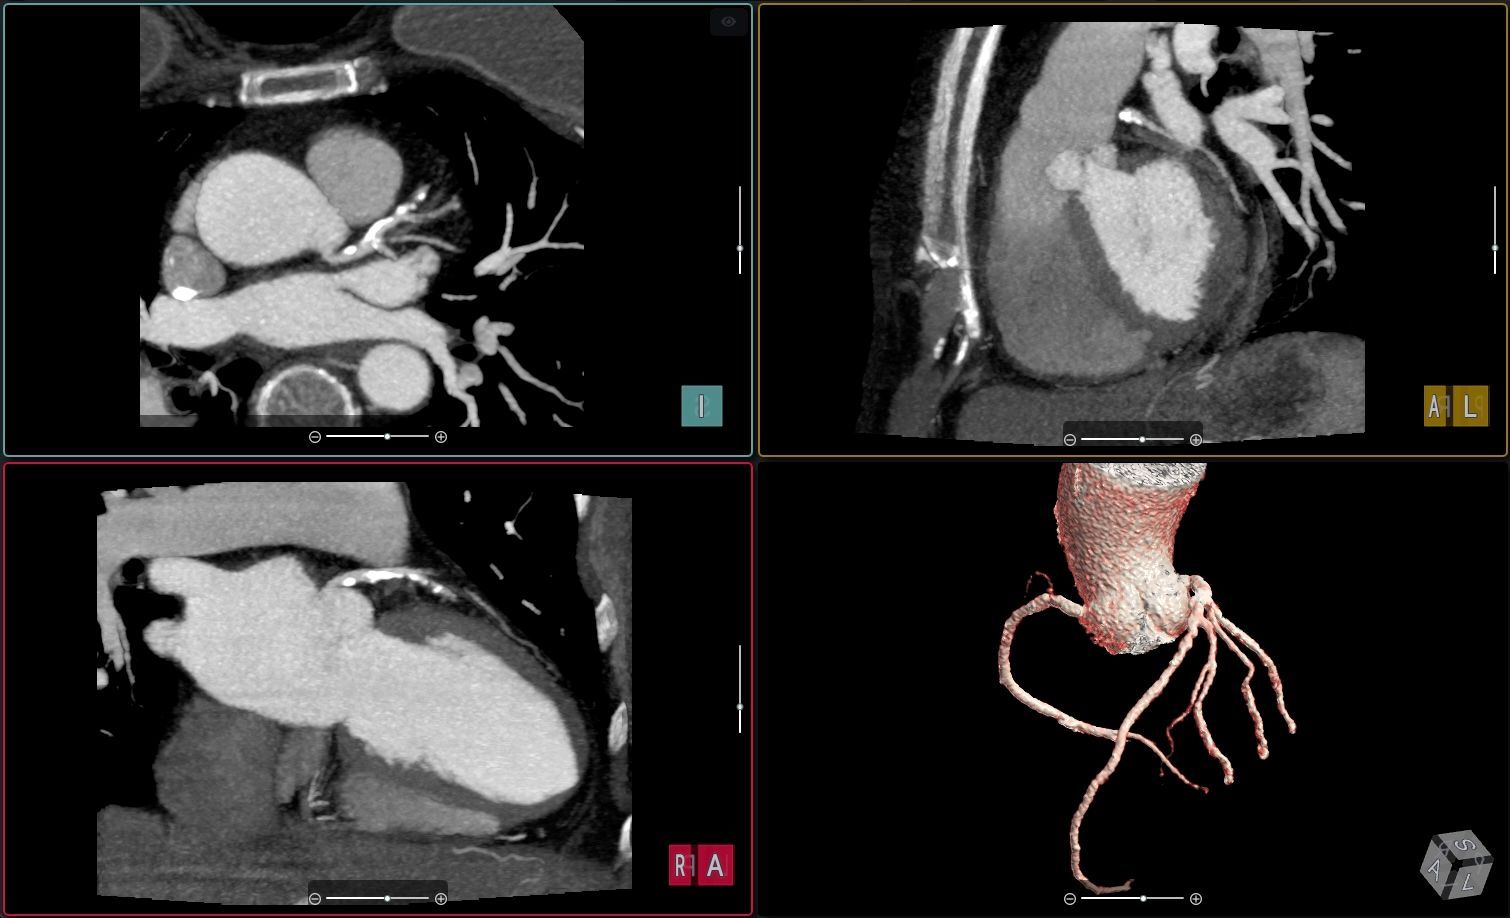

New solution brings advanced vascular analysis into the cvi42 cardiovascular imaging ecosystem. Highlights Circle Cardiovascular Imaging (Circle CVI) has expanded its cvi42 platform to include advanced Vascular CT analysis, integrating Astute Imaging’s AI-driven vascular analysis technology. This enhancement enables comprehensive cardiovascular workflows, allowing clinicians to perform cardiac, vascular, and structural heart analysis within a single, unified platform. This integration supports greater efficiency and collaboration across cardiology, radiology, and vascular surgery teams, advancing the use of quantitative, AI-enabled imaging for diagnosis, procedural planning, and post-treatment management Calgary, AB — March 18, 2026 — Circle Cardiovascular Imaging (Circle CVI) today announced the expansion of its cvi42 cardiovascular imaging platform to include advanced Vascular CT analysis, further extending the platform’s capabilities across cardiovascular imaging workflows. The new solution is enabled through a collaboration with Astute Imaging, whose AI-driven vascular analysis technology has been integrated into the cvi42 ecosystem. The addition of Vascular CT capabilities allows clinicians to analyze complex vascular anatomy for diagnosis, endovascular procedure planning, and post-treatment surveillance, all within the same platform used for cardiac imaging and structural heart planning. Advancing Quantitative Cardiovascular Imaging As healthcare systems increasingly adopt quantitative imaging and AI-enabled workflows, clinicians are seeking integrated platforms that can support the full continuum of cardiovascular care — from diagnosis to procedural planning and long-term disease management. The new Vascular CT capabilities extend the scope of cvi42 beyond cardiac imaging, enabling automated vascular analysis within the same environment trusted by cardiovascular teams worldwide. The technology powering these capabilities was developed by Astute Imaging, whose advanced algorithms support automated segmentation, quantification, and visualization of vascular structures. “Fragmented imaging workflows can slow collaboration and decision making between cardiovascular teams,” said Dr. Kevin Steel, Chief Medical Officer, Circle CVI. “By bringing vascular CT analysis into the cvi42 ecosystem, clinicians can work from the same platform across cardiac and vascular cases, helping improve efficiency and coordination of care.” Cardiac and vascular analysis within a unified workflow helps multidisciplinary cardiovascular teams collaborate more effectively across cardiology, radiology, and vascular surgery. ABOUT CIRCLE CARDIOVASCULAR IMAGING Circle Cardiovascular Imaging Inc. (Circle CVI) is a Canadian-based company founded in 2007 with a mission to develop innovative software solutions that enhance cardiovascular and cerebrovascular imaging analysis and ultimately improve patient care. Circle’s flagship platform, cvi42 , delivers best-in-class image reading and reporting tools for quantitative and qualitative assessment of cardiac MR, cardiac CT, vascular CT, and neuro CT . At the core of Circle’s work is a relentless commitment to empowering healthcare providers with advanced, intuitive tools that lead to better healthcare outcomes. This passion for innovation, rooted in both medicine and technology, drives Circle’s global impact and fuels a culture of excellence. Today, millions of medical imaging exams each year, across 1,700+ hospitals in over 90 countries, are interpreted using Circle’s cvi42 platform. For more information, please visit www.circlecvi.com or contact: marketing@circlecvi.com About Astute Imaging Astute Imaging Inc. is a U.S.-based company founded in 2022 with a mission to become a best-in-class provider of AI-enabled vascular imaging and care management software for healthcare providers and MedTech companies. Astute Imaging delivers a fully automated, AI-enabled workflow supporting diagnostics, surgical planning, and longitudinal patient follow-up. The platform covers all major vascular anatomies, including the aorta, carotid arteries, and peripheral vasculature. In addition, Astute Imaging provides AI-enabled virtual device simulation, allowing surgeons to visualize and automatically identify the most appropriate device for a patient’s anatomy, enabling highly personalized procedural planning and care management. Astute Imaging’s technology is also used by medical device companies for regulatory and research applications, including core lab services and R&D support. For media inquiries, please contact: marketing@astuteimaging.com